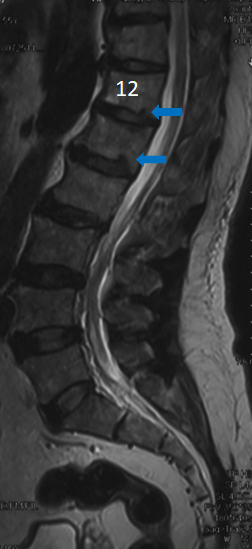

影像资料:

![]()

诊断:

>Scheuermann’s病(II型)

TK=53°>45°

TL=42°>30°

T11/T12/L1楔形变>5°

T12/L1许莫氏结节